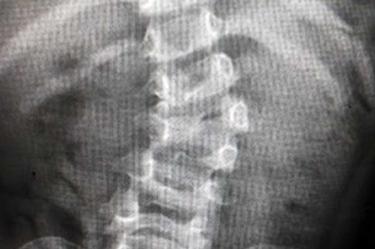

La pequeña Fátima tenía dificultades para desplazarse y mantener una buena postura, ya que su columna vertebral tenía forma de “S”, y sus hombros y caderas estaban desnivelados, pero al cabo de los meses y por la exitosa cirugía, a cargo del equipo multidisciplinario del IMSS, ahora es capaz de correr.

La cirugía, realizada en febrero pasado, consistió en retirar la vértebra con mala formación para lograr la estabilización y alineación de la columna, y con implantes pediátricos se pudo concluir el procedimiento.